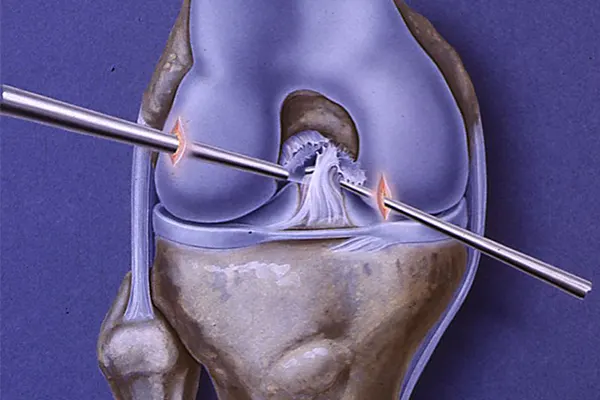

ACL surgery is a surgical procedure aimed at reconstructing or repairing the torn ligament in the center of your knee. The ACL is essential for stabilizing your knee during motion, especially side-to-side or pivoting movements.

In most cases, a graft (taken from your own body or a donor) is used to replace the damaged ligament. The surgery helps restore full knee function, allowing you to walk, run, and return to your active lifestyle.

He uses advanced arthroscopic methods for ACL reconstruction, ensuring minimal damage to surrounding tissues. This approach not only reduces the hospital stay but also speeds up the recovery process.